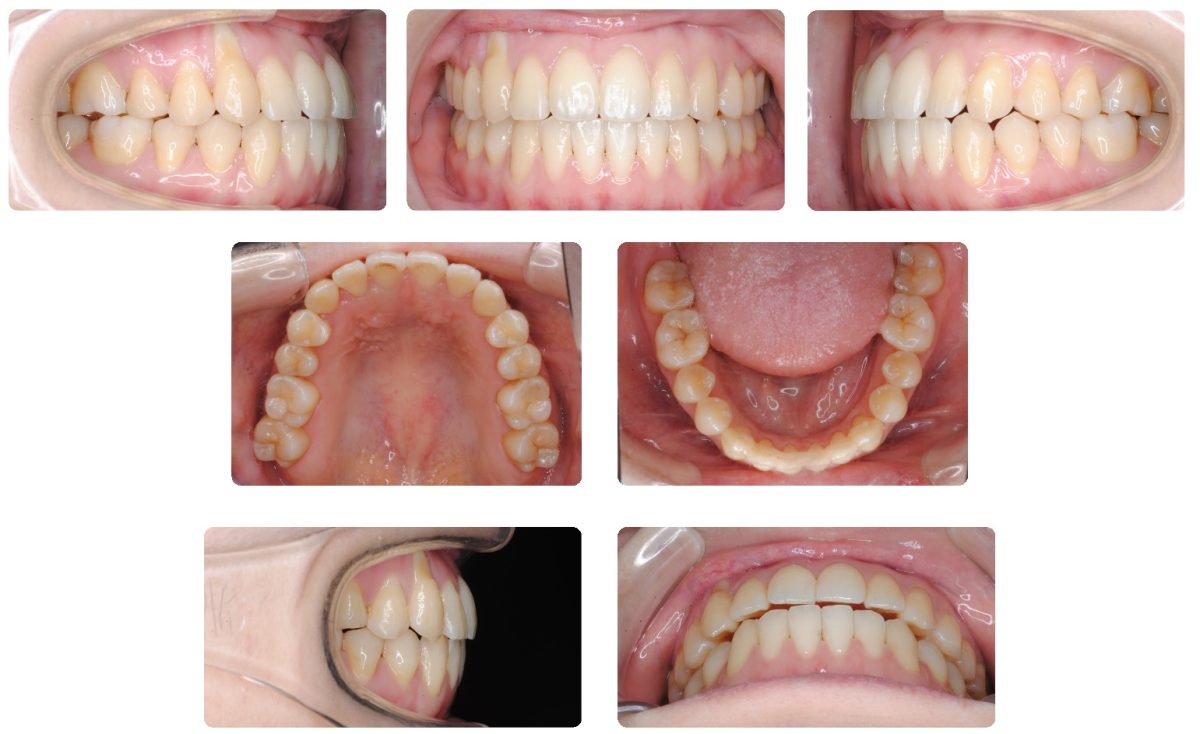

治療期間:1年11ヶ月

動的治療期間は1年11カ月でした。